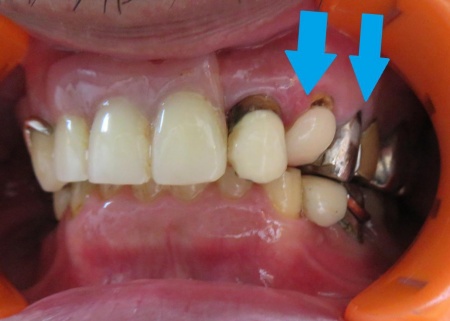

最後に入れ歯を装着し、痛みや違和感がないか、見た目や噛み合わせに問題がないかを確認し、治療を終了しています。

1年前にクラスプの修理をした際の画像です。